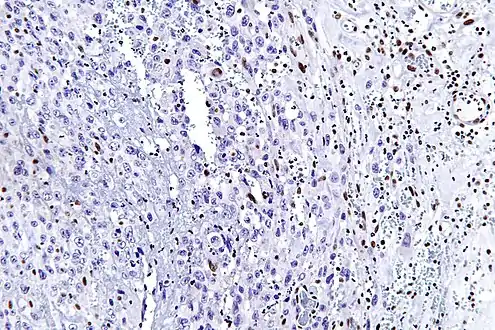

High mag. (SMARCB1)